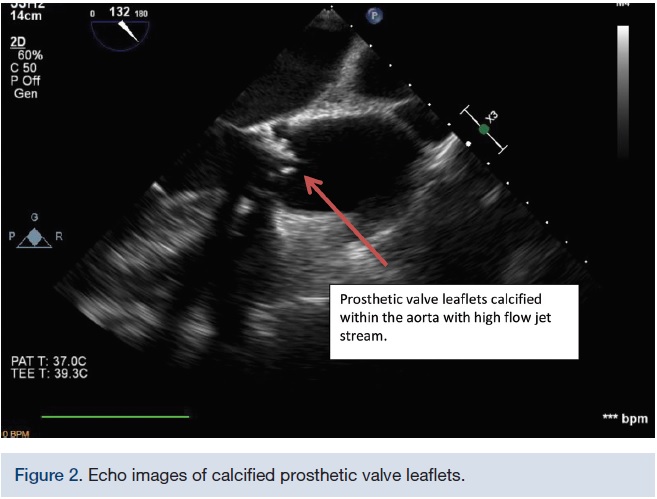

A 2D echocardiogram in February 2016 identified severe stenosis of the prosthetic aortic valve with a mean gradient of 70 mmHg. The left ventricular ejection fraction was normal. Compared to the transthoracic echocardiogram (TTE) in January 2010, there was a significantly higher AV gradient and now a mild to moderate mitral regurgitation. The left ventricle was normal in size and there was moderate concentric left ventricular hypertrophy. The right ventricle was normal in size, thickness, and function. The right ventricular systolic function was normal. The left and right atrial sizes were normal. The mitral valve leaflets appeared thickened, but opened well. There was mild mitral annular calcification and mild to moderate mitral regurgitation. The aortic root was normal in size. The inferior vena cava appeared normal. The aortic valve area was 0.67 cm2.The patient underwent a cardiac catheterization in early March 2016 that showed right coronary artery dominance and a diseased proximal ramus intermedius.

A 2D echo with color flow and doppler was repeated in April 2016, a month post-procedure. A mild to moderate perivalvular regurgitation was noted around the prosthetic aortic valve. There was no gross rocking of the valve, but there was a potential space between the valve and aortic annulus resulting in a mild peri-valvular aortic insufficiency due to the large calcified plaque on the aortic cusp.